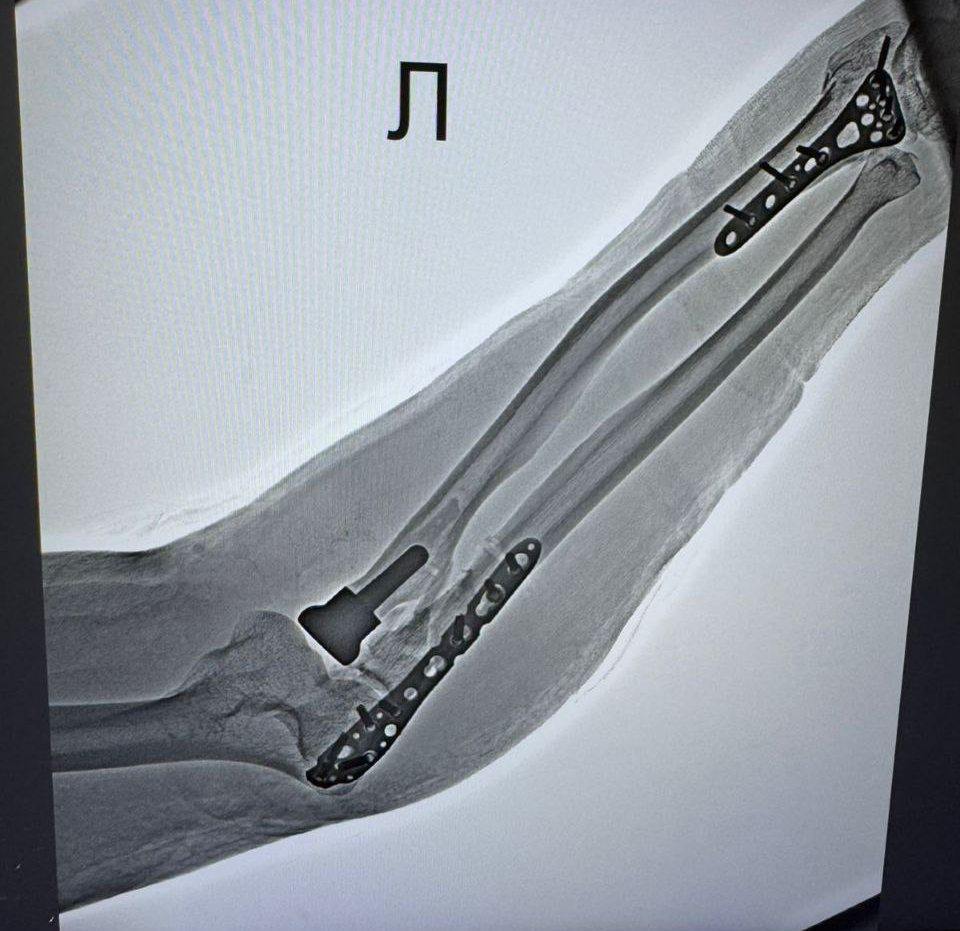

У первой пациентки — 66-летней женщины — был диагностирован оскольчатый перелом головки лучевой кости. У второго — 55-летнего мужчины — дистальный перелом метаэпифиза левой лучевой кости, перелом локтевой кости в верхней трети и оскольчатый перелом головки лучевой кости. Обе травмы были получены в результате неудачного падения.

— При таких травмах крайне сложно выполнить стабилизацию перелома с помощью пластин — так называемый остеосинтез. Поэтому было принято решение провести протезирование головки лучевой кости — вмешательство, требующее высокой точности и опыта врачей. Во время операции удаляются костные осколки, формируется специальное ложе в проксимальном отделе лучевой кости, после чего в него устанавливается эндопротез головки лучевой кости, — рассказал заведующий травматологическим отделением Тавриз Аббасов.

Главное преимущество этой методики — возможность в кратчайшие сроки восстановить полную функцию локтевого сустава. После операции пациенты смогут без ограничений сгибать, разгибать и вращать руку.